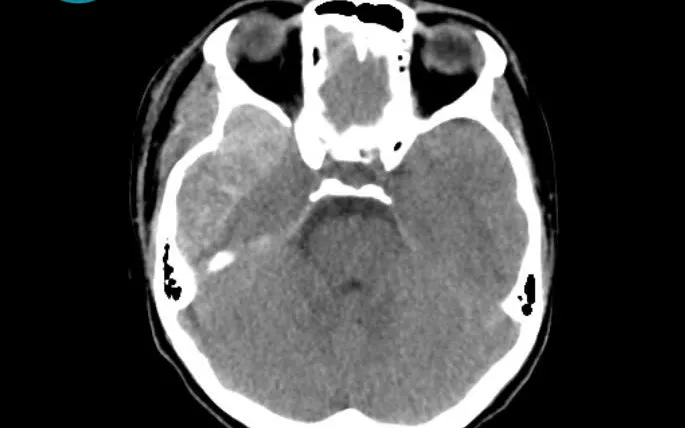

Kết quả chụp CT sọ não ghi nhận khối máu tụ ngoài màng cứng vùng thái dương - đỉnh trái kích thước lớn (78x16x82 mm), kèm tụ khí nội sọ và vỡ xương thái dương.